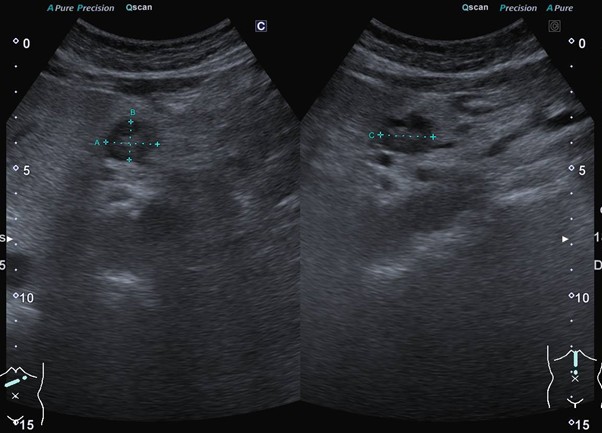

① 腹部エコー検査(腹部超音波検査)

最も手軽で体に負担のない検査です。一番のメリットは、 被曝がなく、短時間で行えることです。膵臓そのものだけでなく、周囲の「胆管の拡張」や「膵管の広がり」をチェックできます。

これらはがんが小さくても現れるサインです。

しかし注意点もあります。 胃や腸のガス、皮下脂肪や内臓脂肪の影響で膵臓の一部が見えにくいことがあります。この場合は、他の画像検査を追加することがあります。

@腹部エコー検査は、このようにおなかに機械を当てるだけで画像が得られます。

@膵がんの症例;膵臓に腫瘤を認めました。